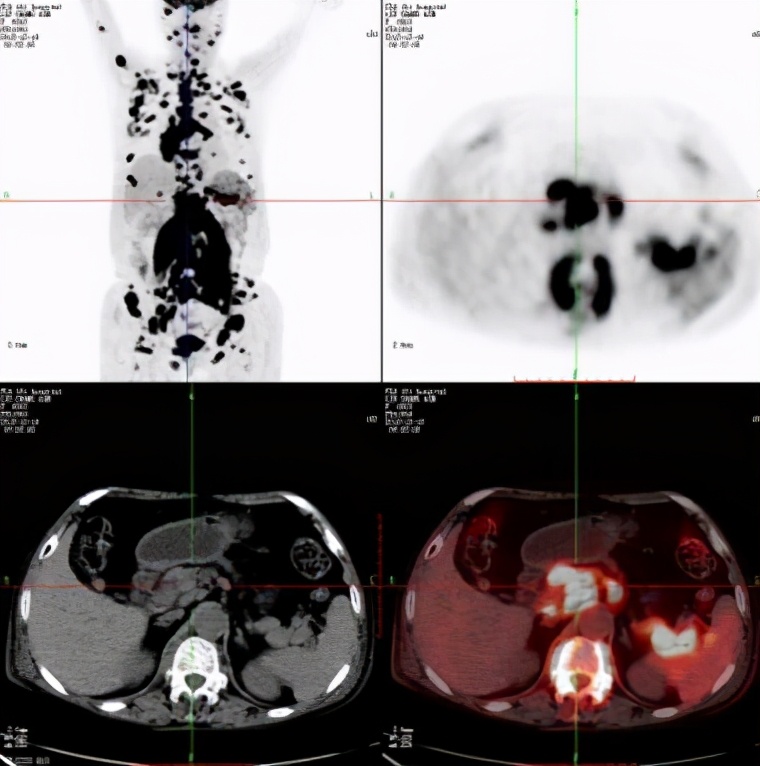

关于PET-CT这个检查,越来越多的人对其有所了解,PET-CT是将PET扫描仪和螺旋CT设备结合在一起形成的功能显像仪器。在肿瘤诊断方面作用尤其突出。PET-CT之所以在肿瘤诊断中有优势,是因为恶性肿瘤细胞代谢率比较高,当带有放射性核素标记的葡萄糖进入体内,会在高代谢区域聚集,形成放射性异常浓聚,从而判断出病变部位。

肺结节同样如此,对于纯磨玻璃结节,即便是恶性的,大多数为贴壁生长的细胞,这类细胞为惰性生长,代谢率很低,在PET-CT上几乎没有FDG的摄取。Fleischner指南认为对于小的纯磨玻璃结节,PET-CT没有诊断价值。而对于对于8mm-10mm的部分实性磨玻璃结节(即混合磨玻璃结节),在进行创伤性的检查前建议进行PET-CT检查。美国胸科医师学(ACCP)肺部结节评估指南提出:对于>8mm的部分实性结节,第3个月复查CT,如果持续存在,可进一步PET-CT检查、非手术活检或手术切除。由此可见,肺结节需不需要做PET-CT是有要求和标准的,8mm以下的肺结节做PET-CT价值不大,还得承受较大的辐射风险,得不偿失。